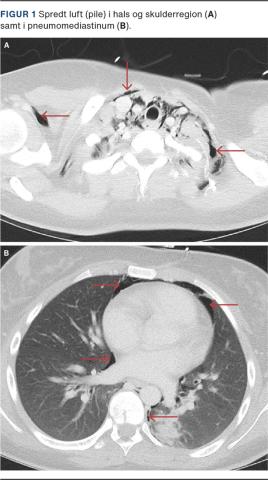

Patienten rettede sig roligt klinisk og paraklinisk de efterfølgende timer, og anion gap var normaliseret efter ca. 12 timer. Patienten var dog fortsat bevidsthedspåvirket, hvorfor der blev udført CT af cerebrum. På dette tidspunkt var patientens respiration upåfaldende. CT af cerebrum var upåfaldende, men der fandtes overraskende luft i halsens strukturer. Dette fund foranledigede CT af hals og thorax, og her blev der fundet:»Luft, der strækker sig opad på begge sider af halsen, anteriort for højre skulder samt i retrofaryngeale og submandibulære rum [Figur 1]. Endvidere luftdissektion langs bronkosvaskulære træ på begge sider samt omkring distale øsofagus og aorta descendens. Lille pneumothorax medialt sin. og små kappepneumothoraces bilateralt«.

Aktuelle »tilfældige« og asymptomatiske fund af luft i patientens hals, pneumomediastinum og pneumothorax blev i dette tilfælde således tilskrevet en lille bronkial utæthed, som var opstået i forbindelse med Kussmauls respiration, stønnen og hosten i forbindelse med patientens diabetiske ketoacidose.